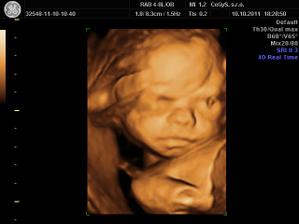

10.10 - 3D u Dr. Hlavacika v CeGys, vysoka spokojnost, mily pristup, krasne fotecky, sme na nasu Misku hrdi - je krasna uz teraz!!! V 25tt vazi o trosku viac ako by mala a to 725g...

No vám to 3D pekne vyšlo a pekne sa ukázala.. škoda, že ten náš sa nechcel tak ukázať a potom sa nám otočil chrbtom ☹

@katrenka111 jeeej, tak gratulujem k Petkovi 😵 A na 3D nepojdete, my sme boli teraz a super to bolo, len mala bola akasi zamracena 😉